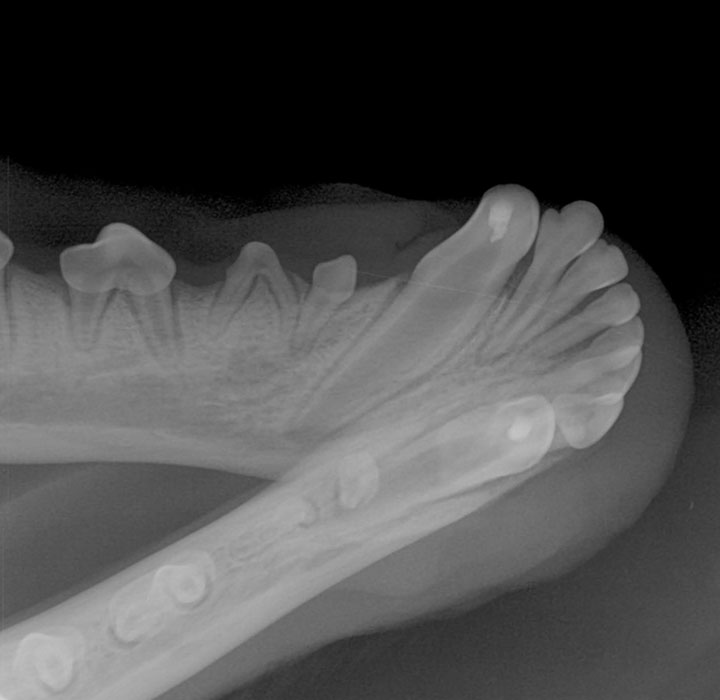

When you think of orthodontics, most people picture metal brackets connected by elastic bands to correct various dental problems, such as a malocclusion (the teeth don’t fit together properly) and crooked teeth. The practice of moving a tooth into a different position in the mouth may sometimes be painful, but the end result can be a prettier smile and a mouth that is healthier and more functional. But why would we fix crooked teeth in a pet?

The answer is: to make a pet’s mouth healthier and less painful. This is a key difference from human orthodontics—we are not aiming for the perfect smile; we are aiming for the most comfortable smile!